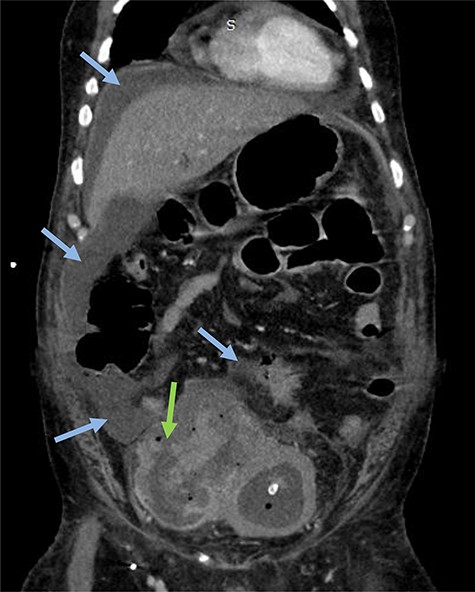

Emergency CT-scan showing intraperitoneal swallowing (blue arrows) due to a fistulization of the bladder (green arrow).